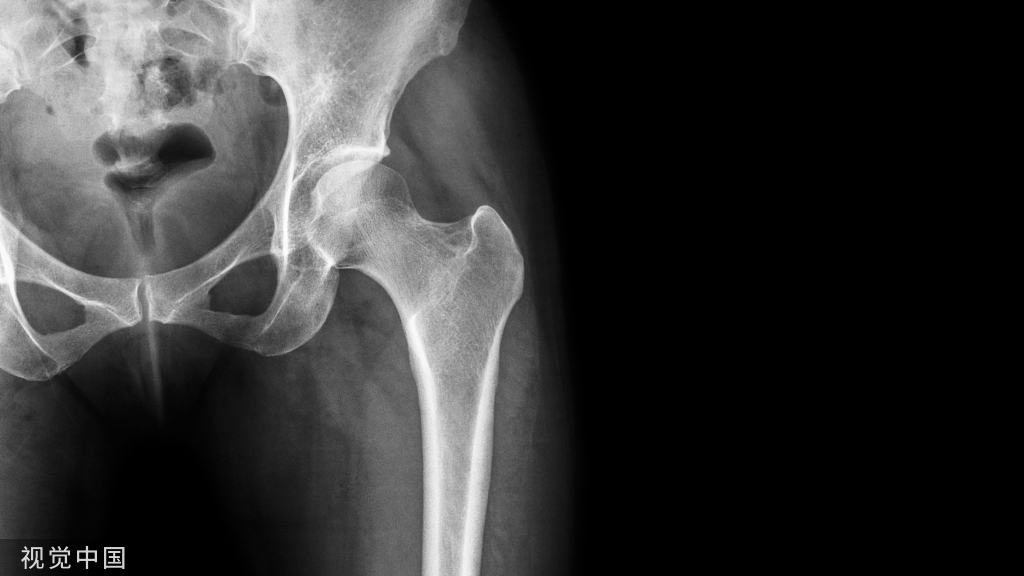

随着医疗水平的进步及人们对生活水平要求的提高,骨科创伤的治疗不仅需要完成局部组织的修复重建,更需要实现机体的快速康复。针对下肢骨科手术,早期进行合理的负重锻炼是术后管理的重要组成部分。合理负重不仅有助于局部骨质及软组织愈合,还可以促进患者整体机能恢复,提高医疗服务效率。然而,在临床实际操作中,如何让下肢术后患者合理负重一直是困扰医生及患者的难题,业内对于下肢术后负重基本理念及注意要点尚未达成共识。

针对此临床问题,由全国创伤骨科专家代表讨论总结了临床中术后负重现有的普遍问题,形成了下肢骨折术后合理负重的基本原则及专家建议,同时列举了针对下肢各部位的负重参考方案,以期指导骨科下肢术后负重临床实践,规范临床研究及相关技术发展,为骨折下肢创伤患者提供更加优质、高效的医疗服务。